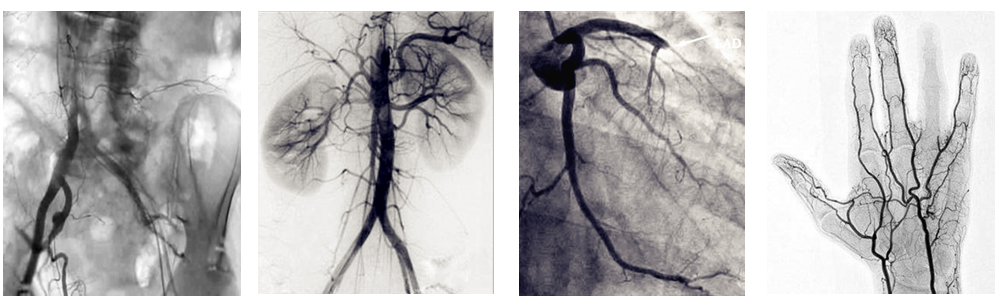

介入c臂機(jī)可以把不需要的組織影像刪除掉,只保留血管影像。圖像清晰,分辨率高,對(duì)觀察血管病變,血管狹窄的定位測(cè)量,診斷及介入治療提供了真實(shí)的立體圖像,還具有多種工作模式,靈活方便,滿足各種臨床需要,為各種介入治療提供了必備條件。

普愛醫(yī)療PLX7100A數(shù)字移動(dòng)式C型臂X射線機(jī)是為周邊介入治療而設(shè)計(jì)的移動(dòng)式平板介入c臂機(jī),配備新型的非晶硅動(dòng)態(tài)平板探測(cè)器,使之成為一款更加貼合介入臨床需求的移動(dòng)式介入設(shè)備。下面小編給大家介紹下我公司介入c臂機(jī)臨床應(yīng)用及性能特點(diǎn):

PLX7100A移動(dòng)式介入c臂機(jī),體積小,劑量低,圖像清晰,是廣大基層醫(yī)院介入腫瘤科以及三甲醫(yī)院??平槿?如肝膽外科、ERCP室、婦科)使用的理想設(shè)備。